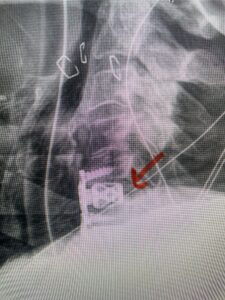

This 61-year-old female with a history of severe osteoporosis and a prior history of a laminectomy from l2-S1 with an L5-S1 instrumented fusion, presents with progressive low back pain and right lower extremity radiculopathy. MRI revealed a grade 1 L2-3 spondylolisthesis with severe stenosis mainly from severe right L2-3 facet joint hypertrophy which was compressing the right L3 descending nerve root. (Fig. 1). She had failed conservative management consisting of physical therapy and pain management with epidurals. She underwent an L1-3 revision laminectomy where we had to dissect a plane underneath the inferior aspect of the L2 lamina. We performed an instrumented fusion at L2-3 with special hydroxyapatite-coated screws to improve fixation to surrounding bone given here severe osteoporosis (Fig. 2) This worked out well and the patient had an uneventful recovery with relief of her leg pain.

Fig: 2a: AP and lateral intraoperative fluoroscopic images demonstrating good placement of L2-3 pedicle screws

Fig. 2b